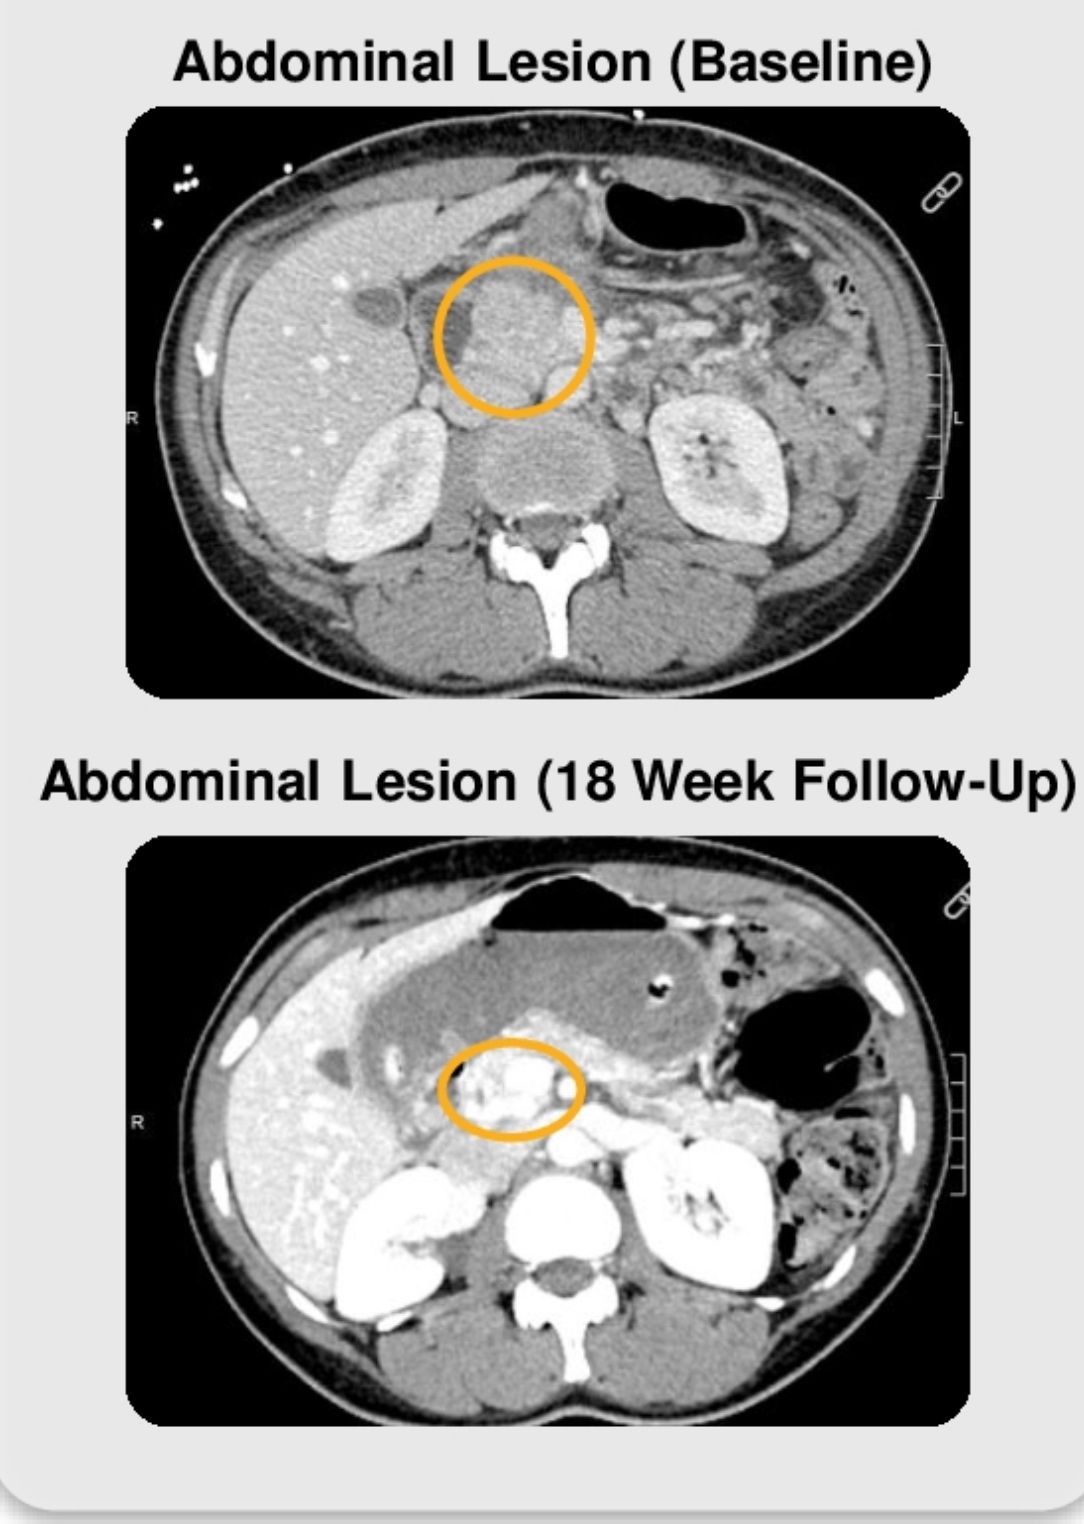

In a recent cohort, the objective response rate (ORR) reached 26% in patients without liver metastases, while 0% ORR was observed in those with hepatic involvement. Confirmed partial responses, including >70% tumor reduction, were seen across KRAS-mutant and wild-type populations. Radiologic data (CT) confirmed substantial shrinkage of abdominal and pulmonary lesions within 9–18 weeks.